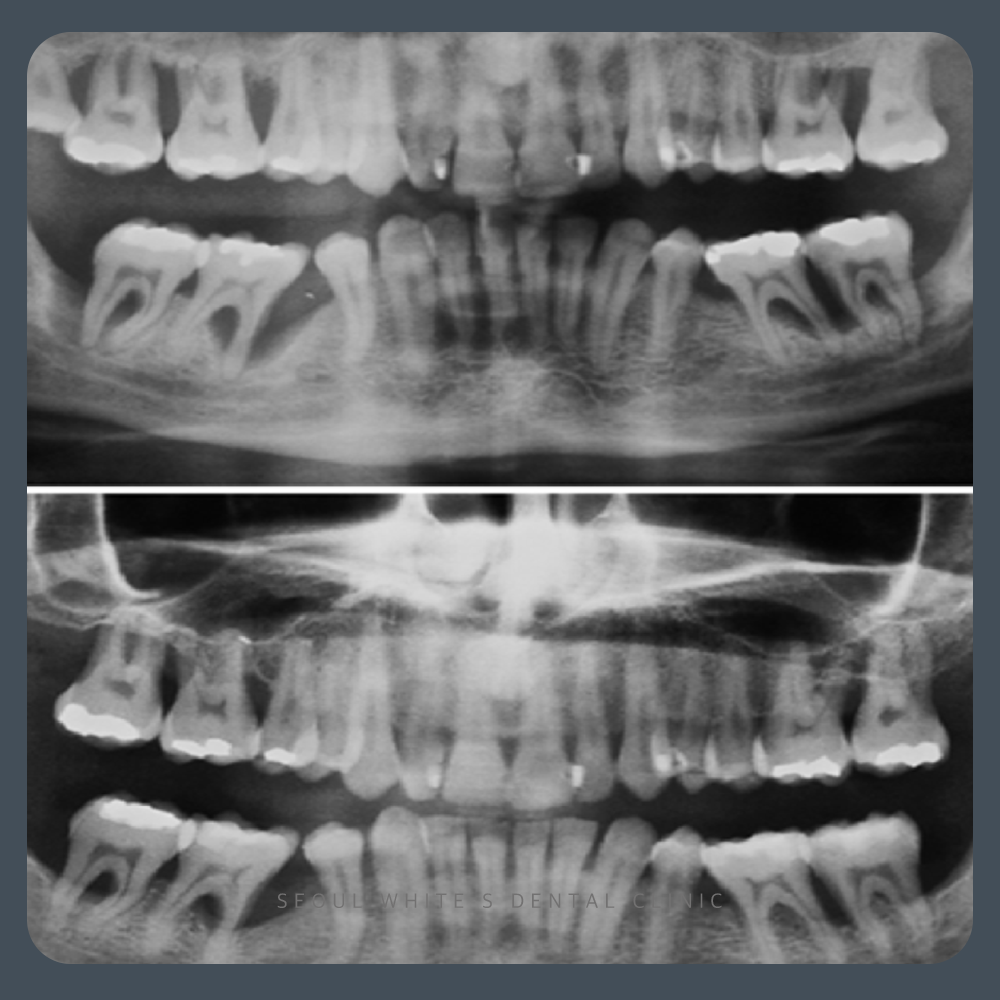

환자분은 몇 년 전부터 양치 중 출혈과 잇몸 붓기를 반복하다가, 최근에는 통증과 간지러움이 생겨서 내원하셨습니다.

환자분께서는 특히 하악 전치부(아랫니 앞부분) 쪽은 부풀고 간지러운 느낌이 지속되어 생활에 큰 불편 느끼고 계셨습니다 염증으로 인한 잇몸 조직의 손상을 줄이고, 세균과 노폐물이 다시 쌓이지 않도록 관리하는 데 중점을 둔 치료입니다. 하지만 이미 치아 주위의 뼈가 파괴된 경우, 이를 치료만으로 온전히 되살리는 것은 어렵습니다. 그렇기 때문에 조기에 발견하고 대응하는 것이 가장 중요합니다. 그렇다면 염증이 있는 상태를 그대로 두면 어떻게 될까요?

염증을 많이 가라앉히고 남은 뼈를 최대한 보존하여, 치아를 유지하였습니다! 염증으로 인한 잇몸 조직의 손상을 줄이고, 세균과 노폐물이 다시 쌓이지 않도록 관리하는 데 중점을 둔 치료입니다. 하지만 이미 치아 주위의 뼈가 파괴된 경우, 이를 치료만으로 온전히 되살리는 것은 어렵습니다. 그렇기 때문에 조기에 발견하고 대응하는 것이 가장 중요합니다. 그렇다면 염증이 있는 상태를 그대로 두면 어떻게 될까요? 경험상, 잇몸 질환에서 발생하는 염증은 저절로 사라지지 않으며, 시간이 갈수록 진행성이 강해져 상태가 더 나빠지는 경우가 많습니다.

영선동잇몸치료는 단순히 잇몸을 청소하는 과정이 아닙니다. 환자분의 잇몸 구조, 염증 정도, 치조골 손실 범위에 따라 치료 범위와 계획이 달라지며, 정밀한 진단이 매우 중요한 치료입니다.